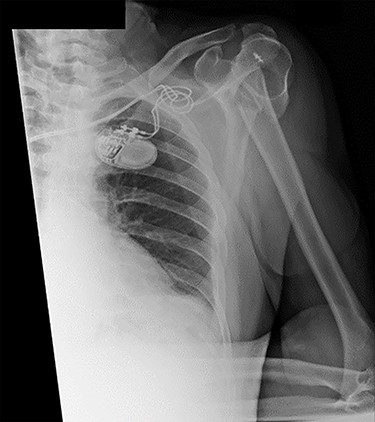

An X-ray of the left shoulder was performed, which revealed acceptable positioning of the fracture. Following a discussion with the patient, a mutual decision was made to manage the injury non-operatively and he was discharged with a collar and cuff sling. Subsequent clinical and radiological review at 1 week and 2 weeks post-injury showed the soft tissues to be healing well and the fracture to be well-positioned (Figs 5 and 6).

Antero-posterior view X-ray taken 2 weeks post-injury showing acceptable positioning of the fracture.